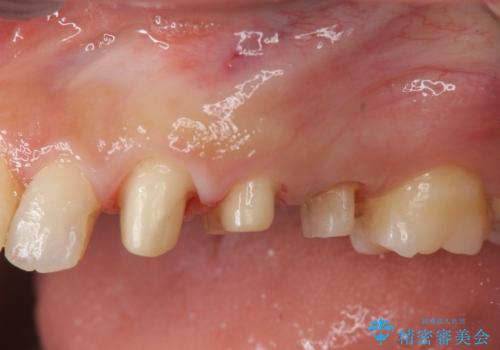

- 歯ぐきの腫れや、歯の内部が黒く見えることからの虫歯の治療を求めて来院されました。

虫歯が大きかったことから、神経の温存はできたものの歯ぐきよりも深い虫歯の問題を解決するため、部分矯正治療を併用したセラミック治療を行うこととしました。

当初、歯ぐきよりも深い虫歯の存在や、歯のポジションに問題がありましたがマルチブラケットを用いた部分矯正で行うことで歯の挺出同時に適切な位置へと歯を移動させ、歯周環境を整えたセラミック治療を行うことができました。